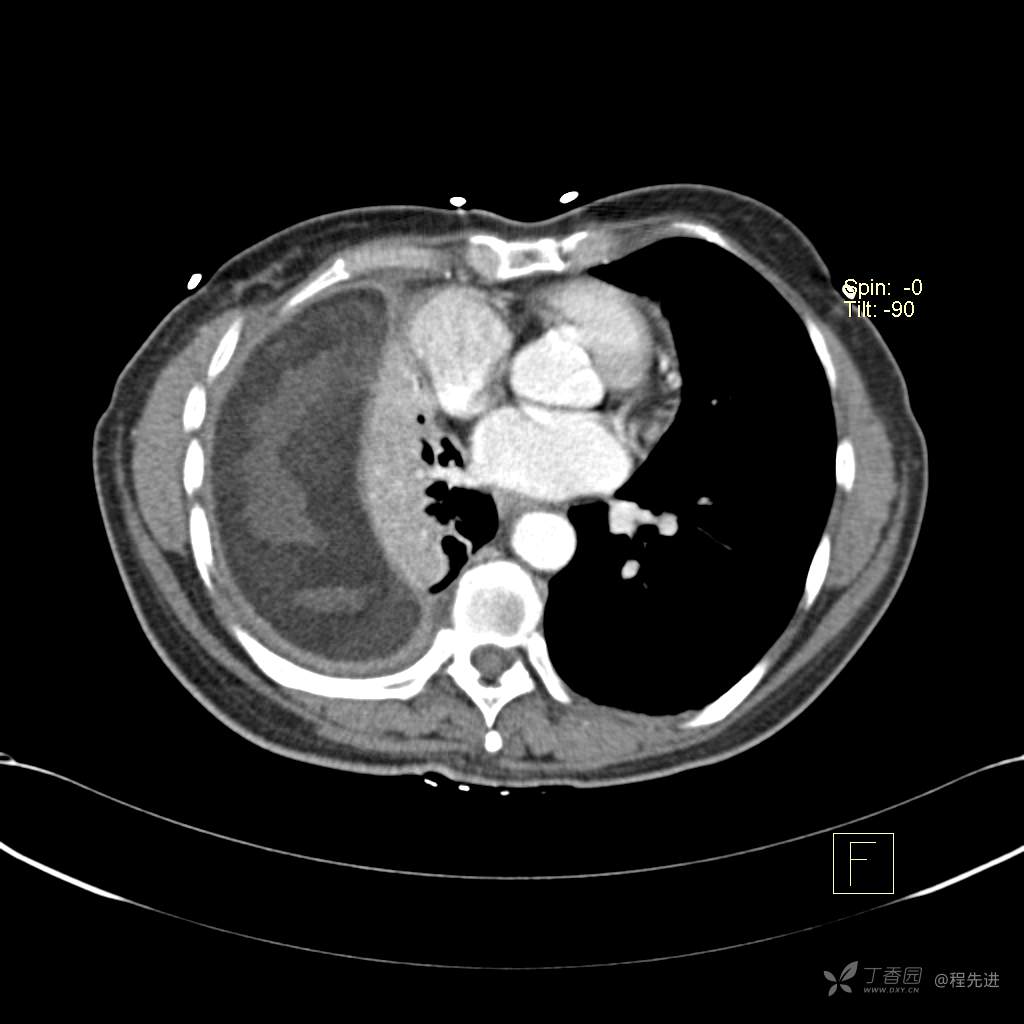

患者性别:女

患者年龄:51岁

简要病史:胸闷半年

肺淋巴管肌瘤病 (7)

乳糜胸 (8)